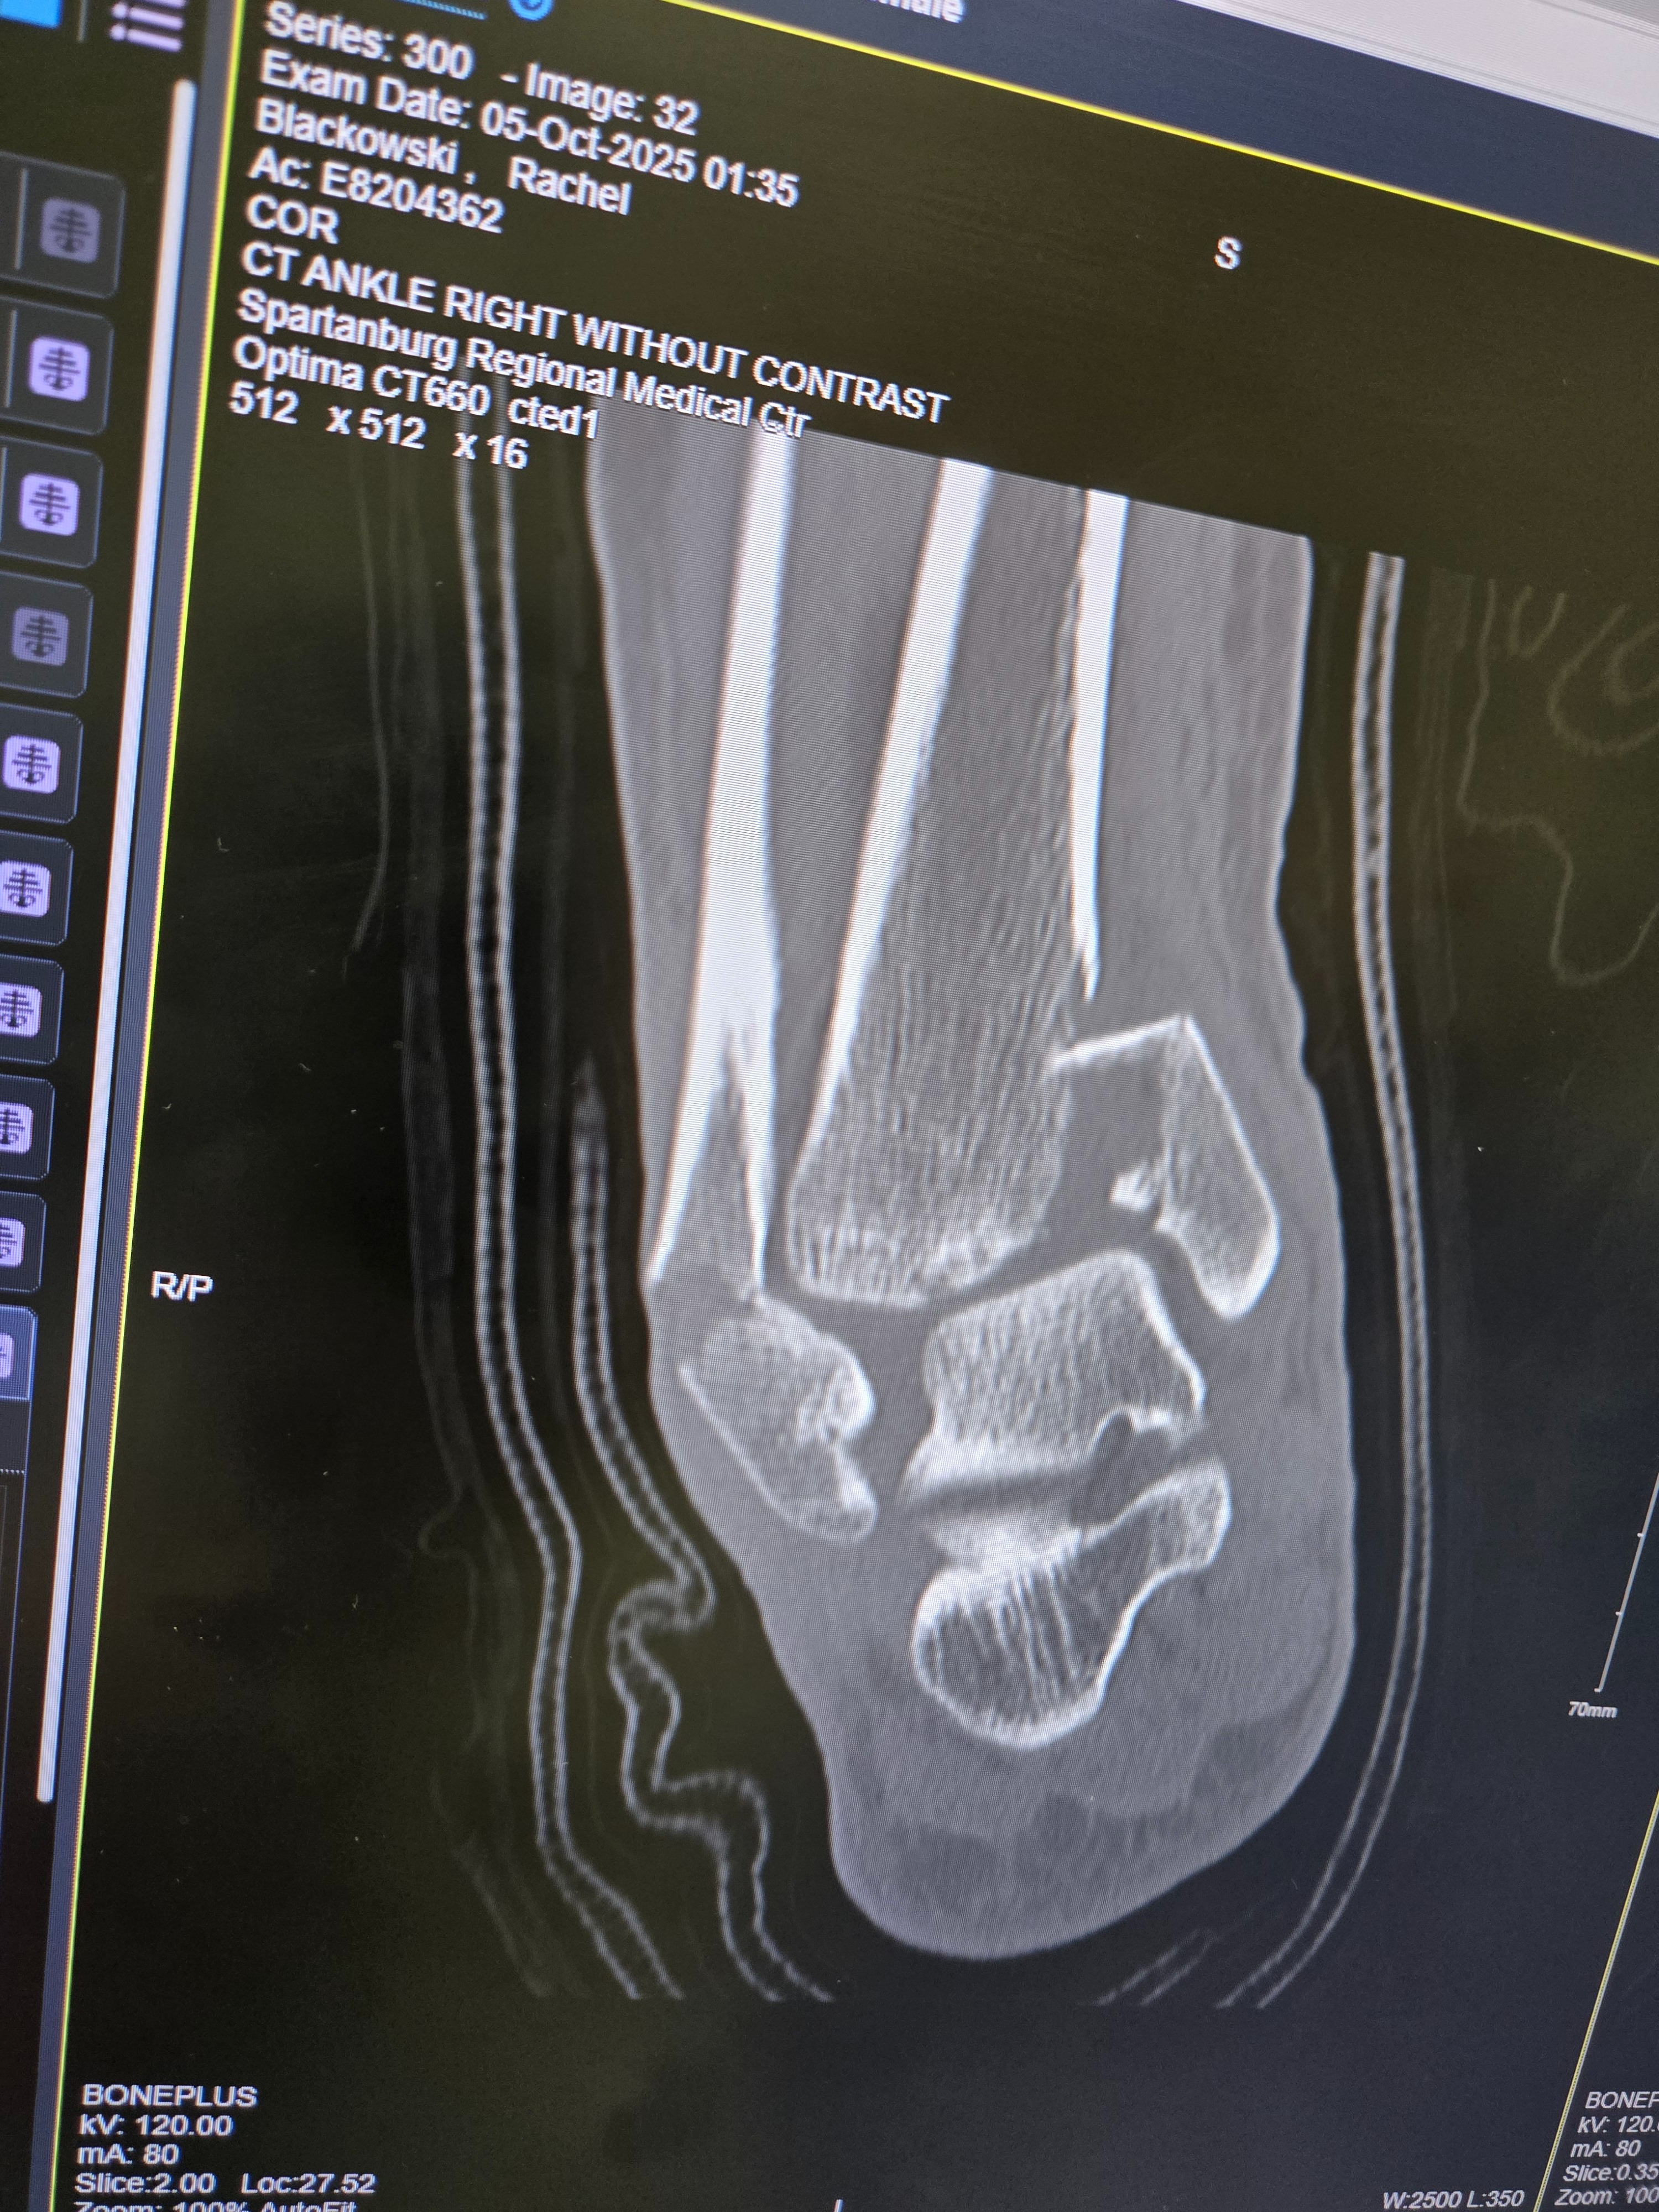

I SURVIVED!!!! My name is Rachel Blackowski, 31 years young.. I was in a severe car accident on Oct 4th . Spent a week in the hospital and have been in rehab. Broken wrist on the left hand (& I'm a lefty) Broken right leg, ankle and knee, non weight bearing injuries for both have me in the wheelchair for an estimated 12 weeks. Have gone through 3 surgeries so far with more to come. Looking at a 6-8 months minimum recovery. Unable to work to provide living wages & owe medical bills. Usually I would be too stubborn & prideful to ask for help ... but this has humbled me to realize I need to lean onto others in my time of need and it is okay. Thank you for any help offered.